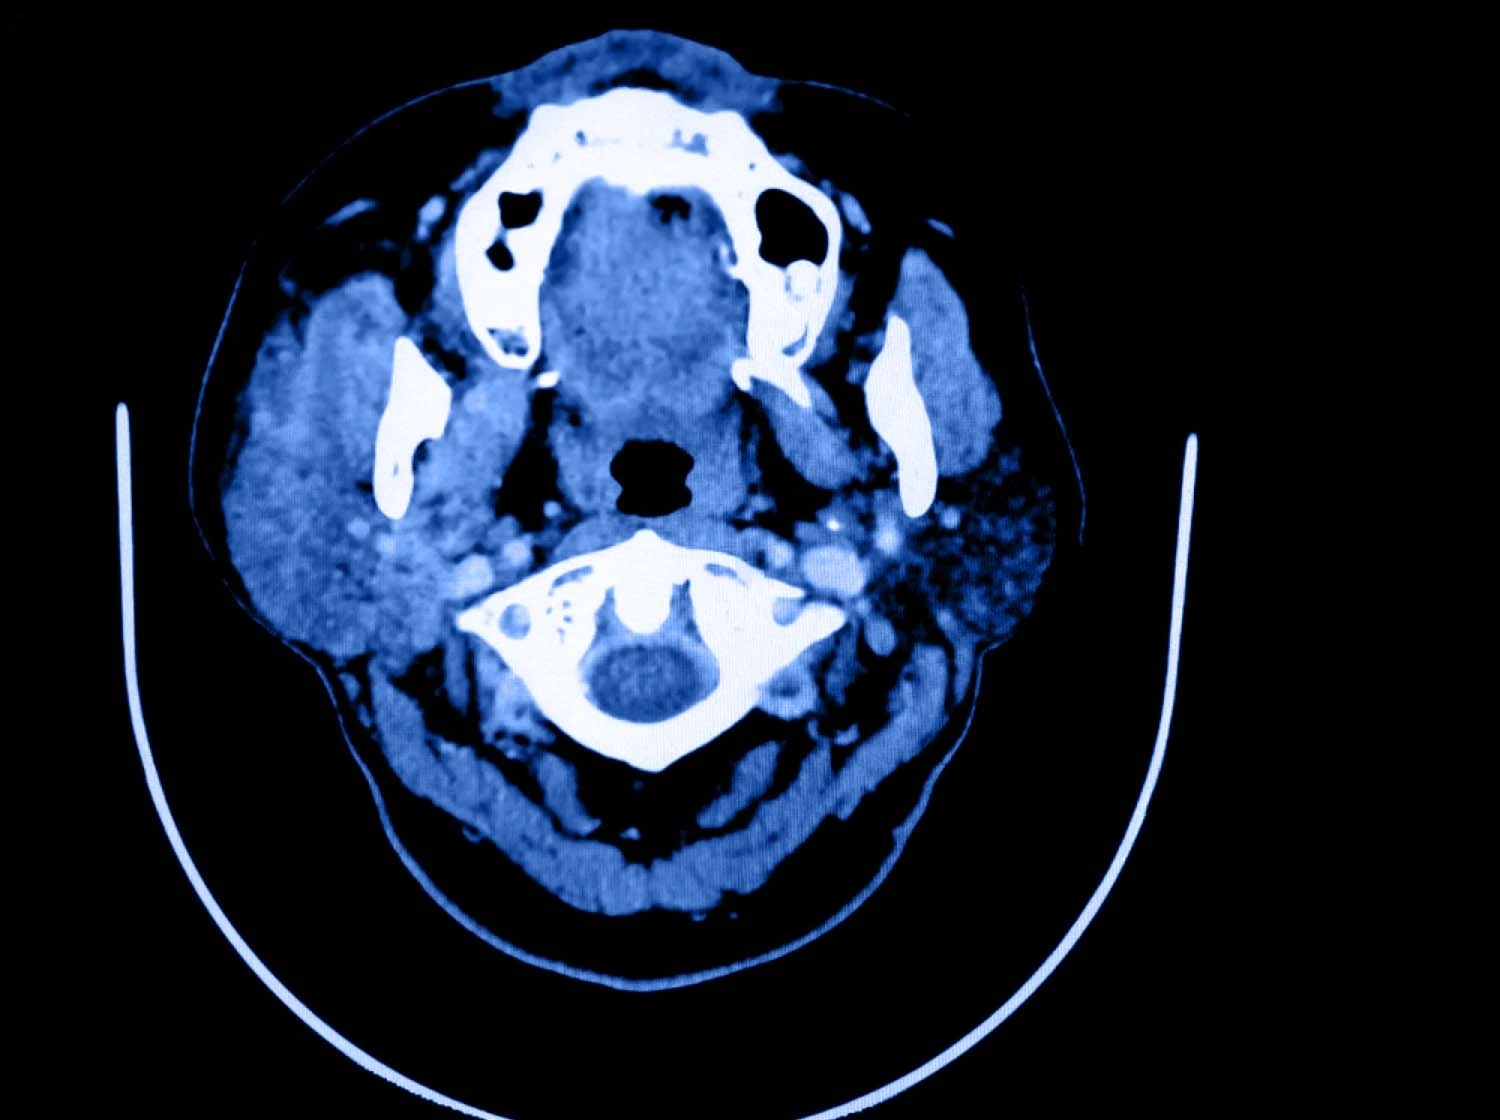

• Estudios de imagen: estudios como la ecografía, resonancia magnética o tomografía computarizada permiten evaluar la localización exacta, su tamaño, forma y relación con estructuras vecinas.

Resonancia magnética de paciente con adenoma pleomorfo, donde se visualiza crecimiento de la glándula parotídea.